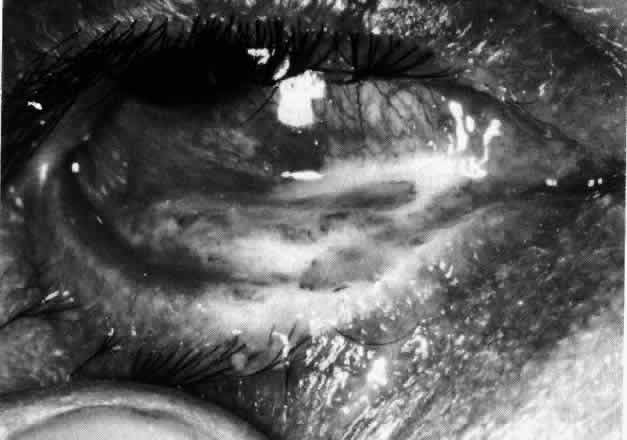

Necrotizing anterior scleritis without adjacent inflammation appears to be a well-defined condition with little relation in clinical features to necrotizing scleral disease, even though the pathology is similar and the final result is the same. Scleromalacia perforans is characterized by the almost total lack of any symptoms. It occurs almost exclusively in patients with long-standing polyarticular rheumatoid arthritis, the majority of whom are female (Figs. 49 and 50; Color Plate 1E).

The anterior sclera loses its covering of episclera and develops an area of yellow-white necrotic slough over many months; this eventually separates or is absorbed, leaving the underlying choroid covered by either conjunctiva or nothing at all. As with necrotizing disease, the choroid does not bulge into this ectatic area; but unlike necrotizing disease, spontaneous healing of even small perforations is very limited once the necrotic tissue has been removed (see Fig. 50).

Fluorescein angiography is not helpful, except to indicate areas of vascular closure in an otherwise extremely thin, atrophic episcleral tissue.4 The formation of a sequestrum appears to be caused by arteriolar closure as opposed to the venular disease seen in the other forms of necrotizing scleritis.